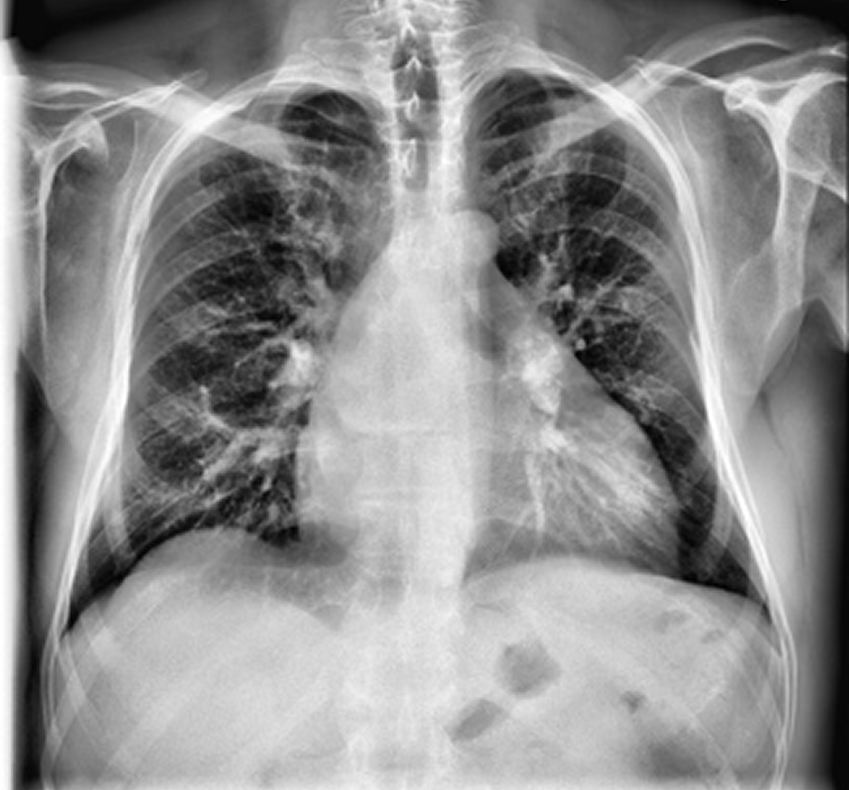

For images flagged as abnormal, a Faster R-CNN model highlights suspicious regions within the lungs. Bounding boxes and heatmaps focus attention on nodules, opacities, masses, and other radiographic abnormalities.